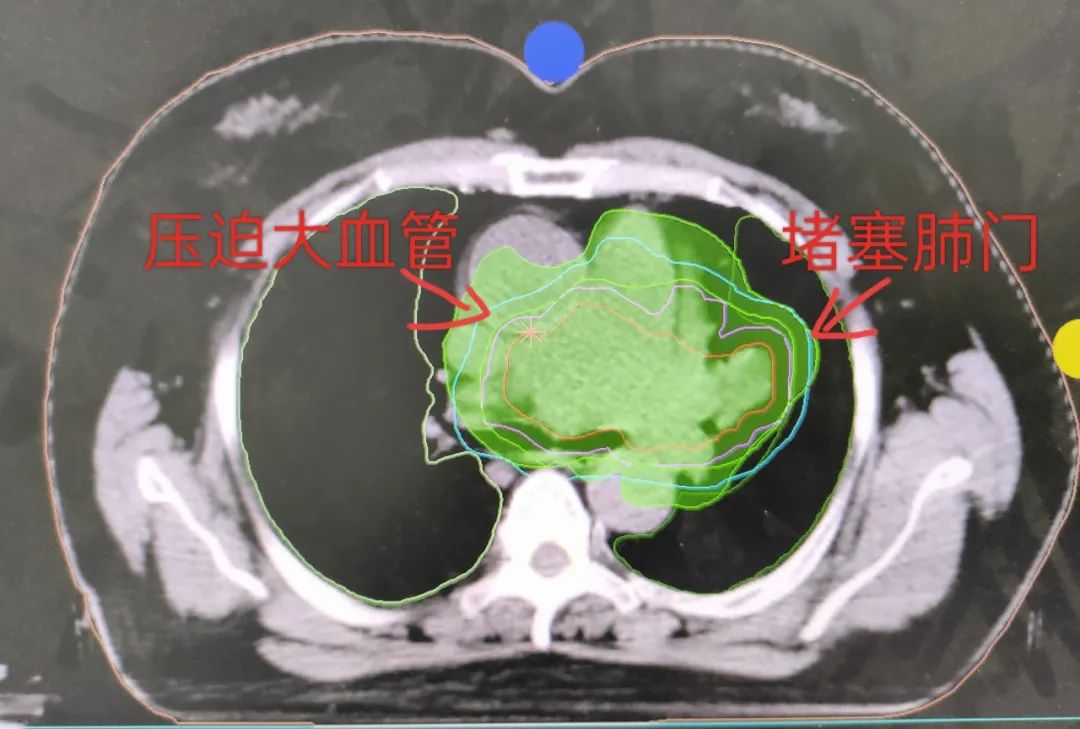

治疗前肺部CT

(注:治疗前肺部病灶压迫大血管、堵塞肺门)

(注:绿色区域为肿瘤放疗区域截面图)

治疗后肺部CT

(注:肿瘤明显缩小,胸闷气短症状消失)